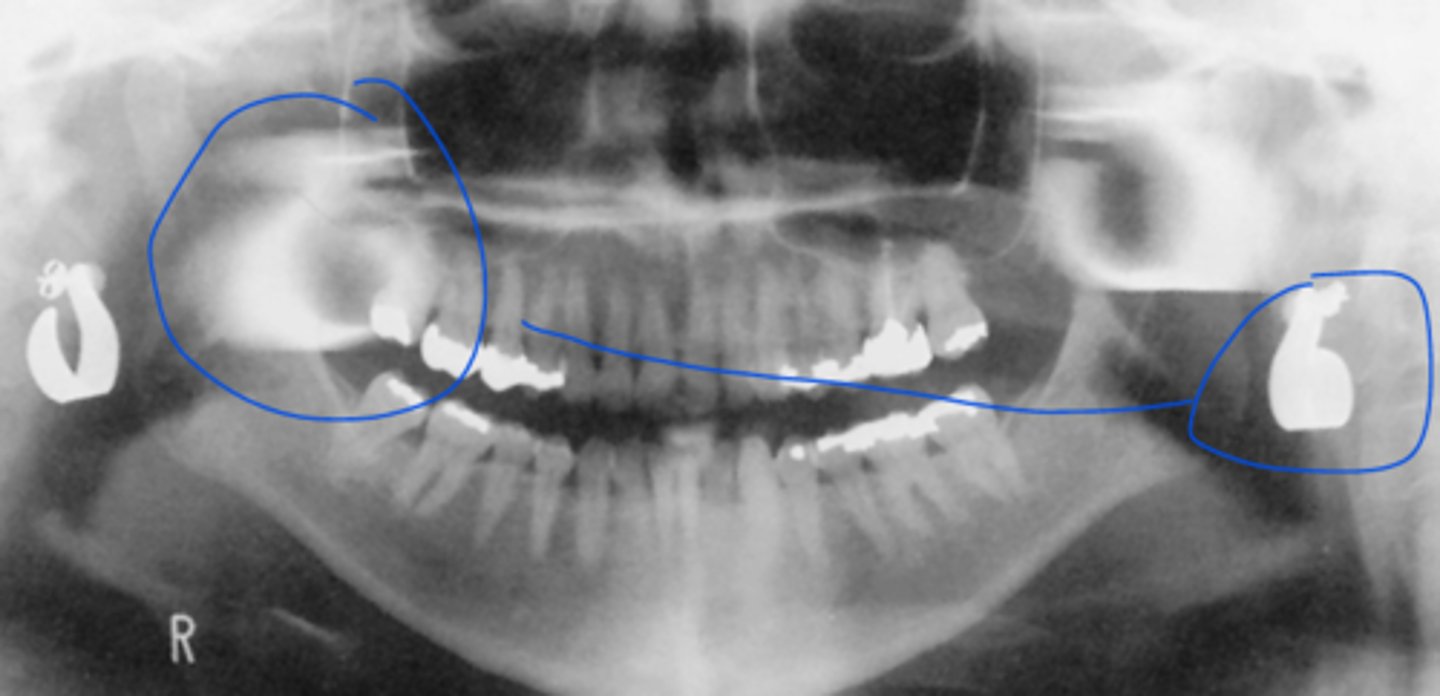

B) double real image

The structures outlined in green indicate what type of image?

A) real image

C) ghost image

The structures outlined in blue indicate what type of image?

The structures outlined in orange indicate what type of image?